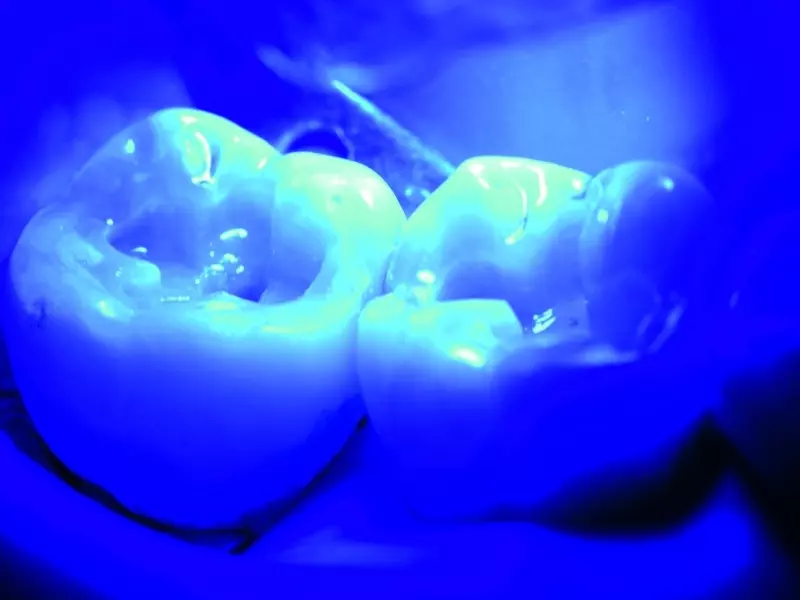

Używając formówek i klinów w obrębie ściany mezjalnej i dystalnej, odbudowano listewki brzeżne pojedynczymi warstwami materiału, a następnie polimeryzowano je przez 20 sekund światłem o natężeniu 1000 mW/cm2 (zdj. 7 i 8). Później wypełniono ubytek niemal całkowicie pojedynczą grubą warstwą. Następnie jedną cienką warstwę wykorzystano w celu ostatecznego wyrzeźbienia powierzchni żujących (zdj. 9–11). Zanim przeprowadzono polimeryzację pierwszej warstwy, wstępnie uformowano bruzdy, co ułatwiło orientację podczas formowania ostatecznej warstwy kompozytu. Wykorzystano do tego bardzo cienki zgłębnik. Tę warstwę również polimeryzowano przez 20 sekund.

Następnie nałożono ostatnią cienką warstwę, którą uformowano i poddano polimeryzacji (zdj. 12–14). W celu uzyskania wrażenia głębi i bardziej naturalnego wyglądu wykorzystano kompozyt FinalTouch firmy VOCO do indywidualnej koloryzacji bruzd (zdj. 15). Potem przeprowadzono ostateczną polimeryzację, trwającą 60 sekund.